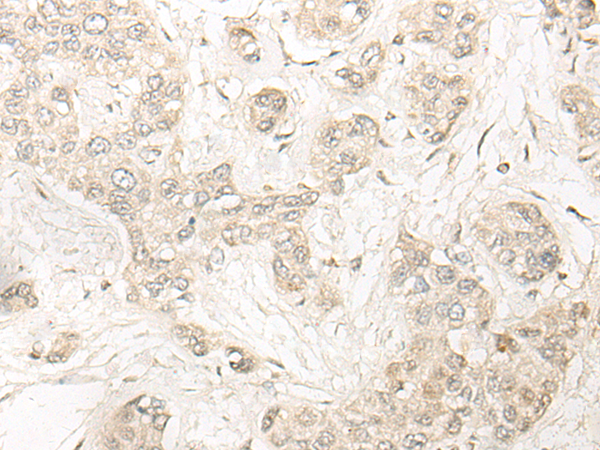

IHC positive control:

Human lung cancer and Human liver cancer

IHC Recommend dilution:

20-100